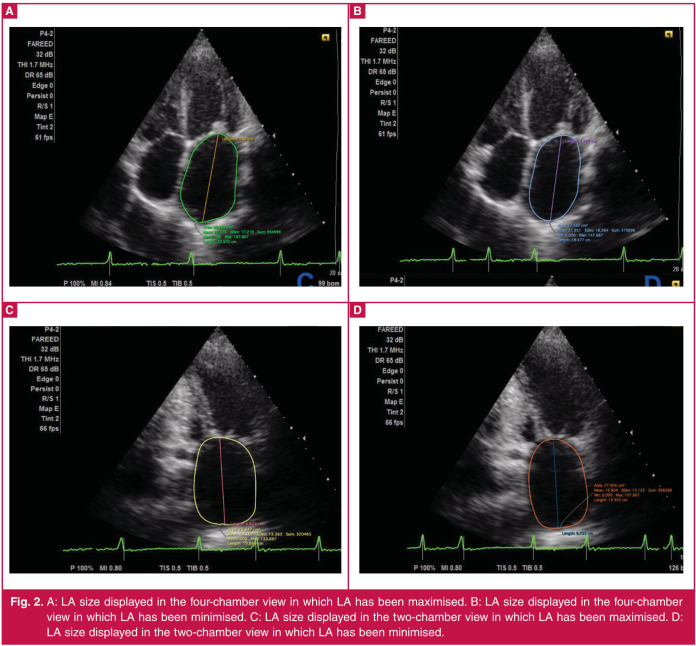

Aim: The aim of this study was to evaluate the association between LA function and mitral valve area (MVA) in rheumatic MS patients, and to assess the echocardiographic parameters in sinus rhythm and atrial fibrillation (AF) patients.

Methods: This was a cross-sectional, descriptive study that involved patients with rheumatic MS. Patients underwent a standard 12-lead electrocardiogram and echocardiographic examination. MVA was assessed and correlated with LA function. Comparison was made between sinus rhythm and AF patients.